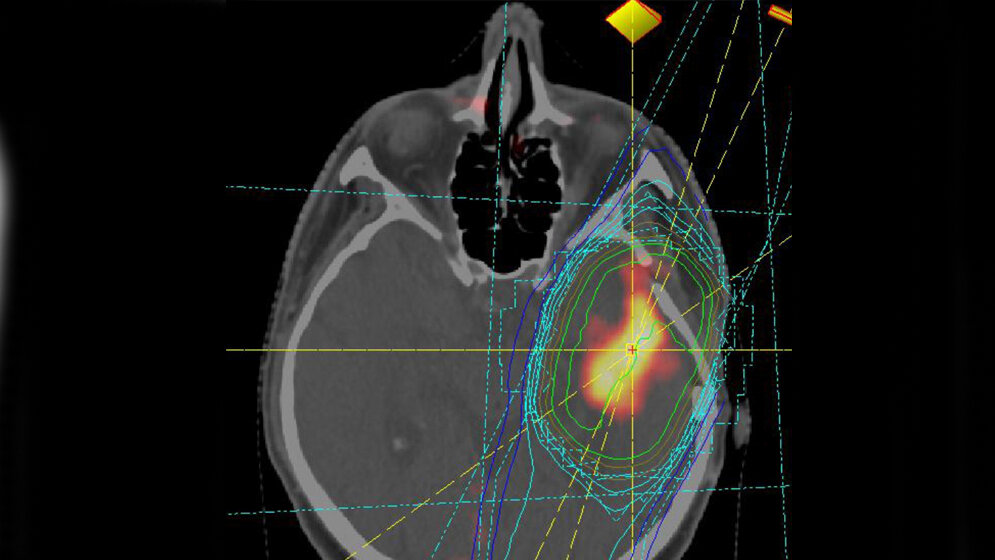

Diagnostizieren Ärzte einen Hirntumor, handelt es sich etwa in jedem fünften Fall um ein Glioblastom. Damit ist diese aggressive Form die häufigste und stellt Ärzte immer noch vor große Herausforderungen. Molekulare Marker könnten dabei helfen, die richtige Therapieentscheidung zu treffen. Forscherinnen und Forscher um Dr. Kristian Unger, stellvertretender Leiter der Abteilung Strahlenzytogenetik (Leiter: Prof. Dr. Horst Zitzelsberger) am Helmholtz Zentrum München, und Prof. Dr. Claus Belka, Direktor der Klinik und Poliklinik für Strahlentherapie und Radioonkologie des Klinikums der Universität München am Campus Großhadern (Mitglied des DKTK Krebsforschungskonsortiums), konnten nun bestimmte miRNAs* identifizieren, die als Biomarker für den Verlauf der Krankheit dienen könnten.